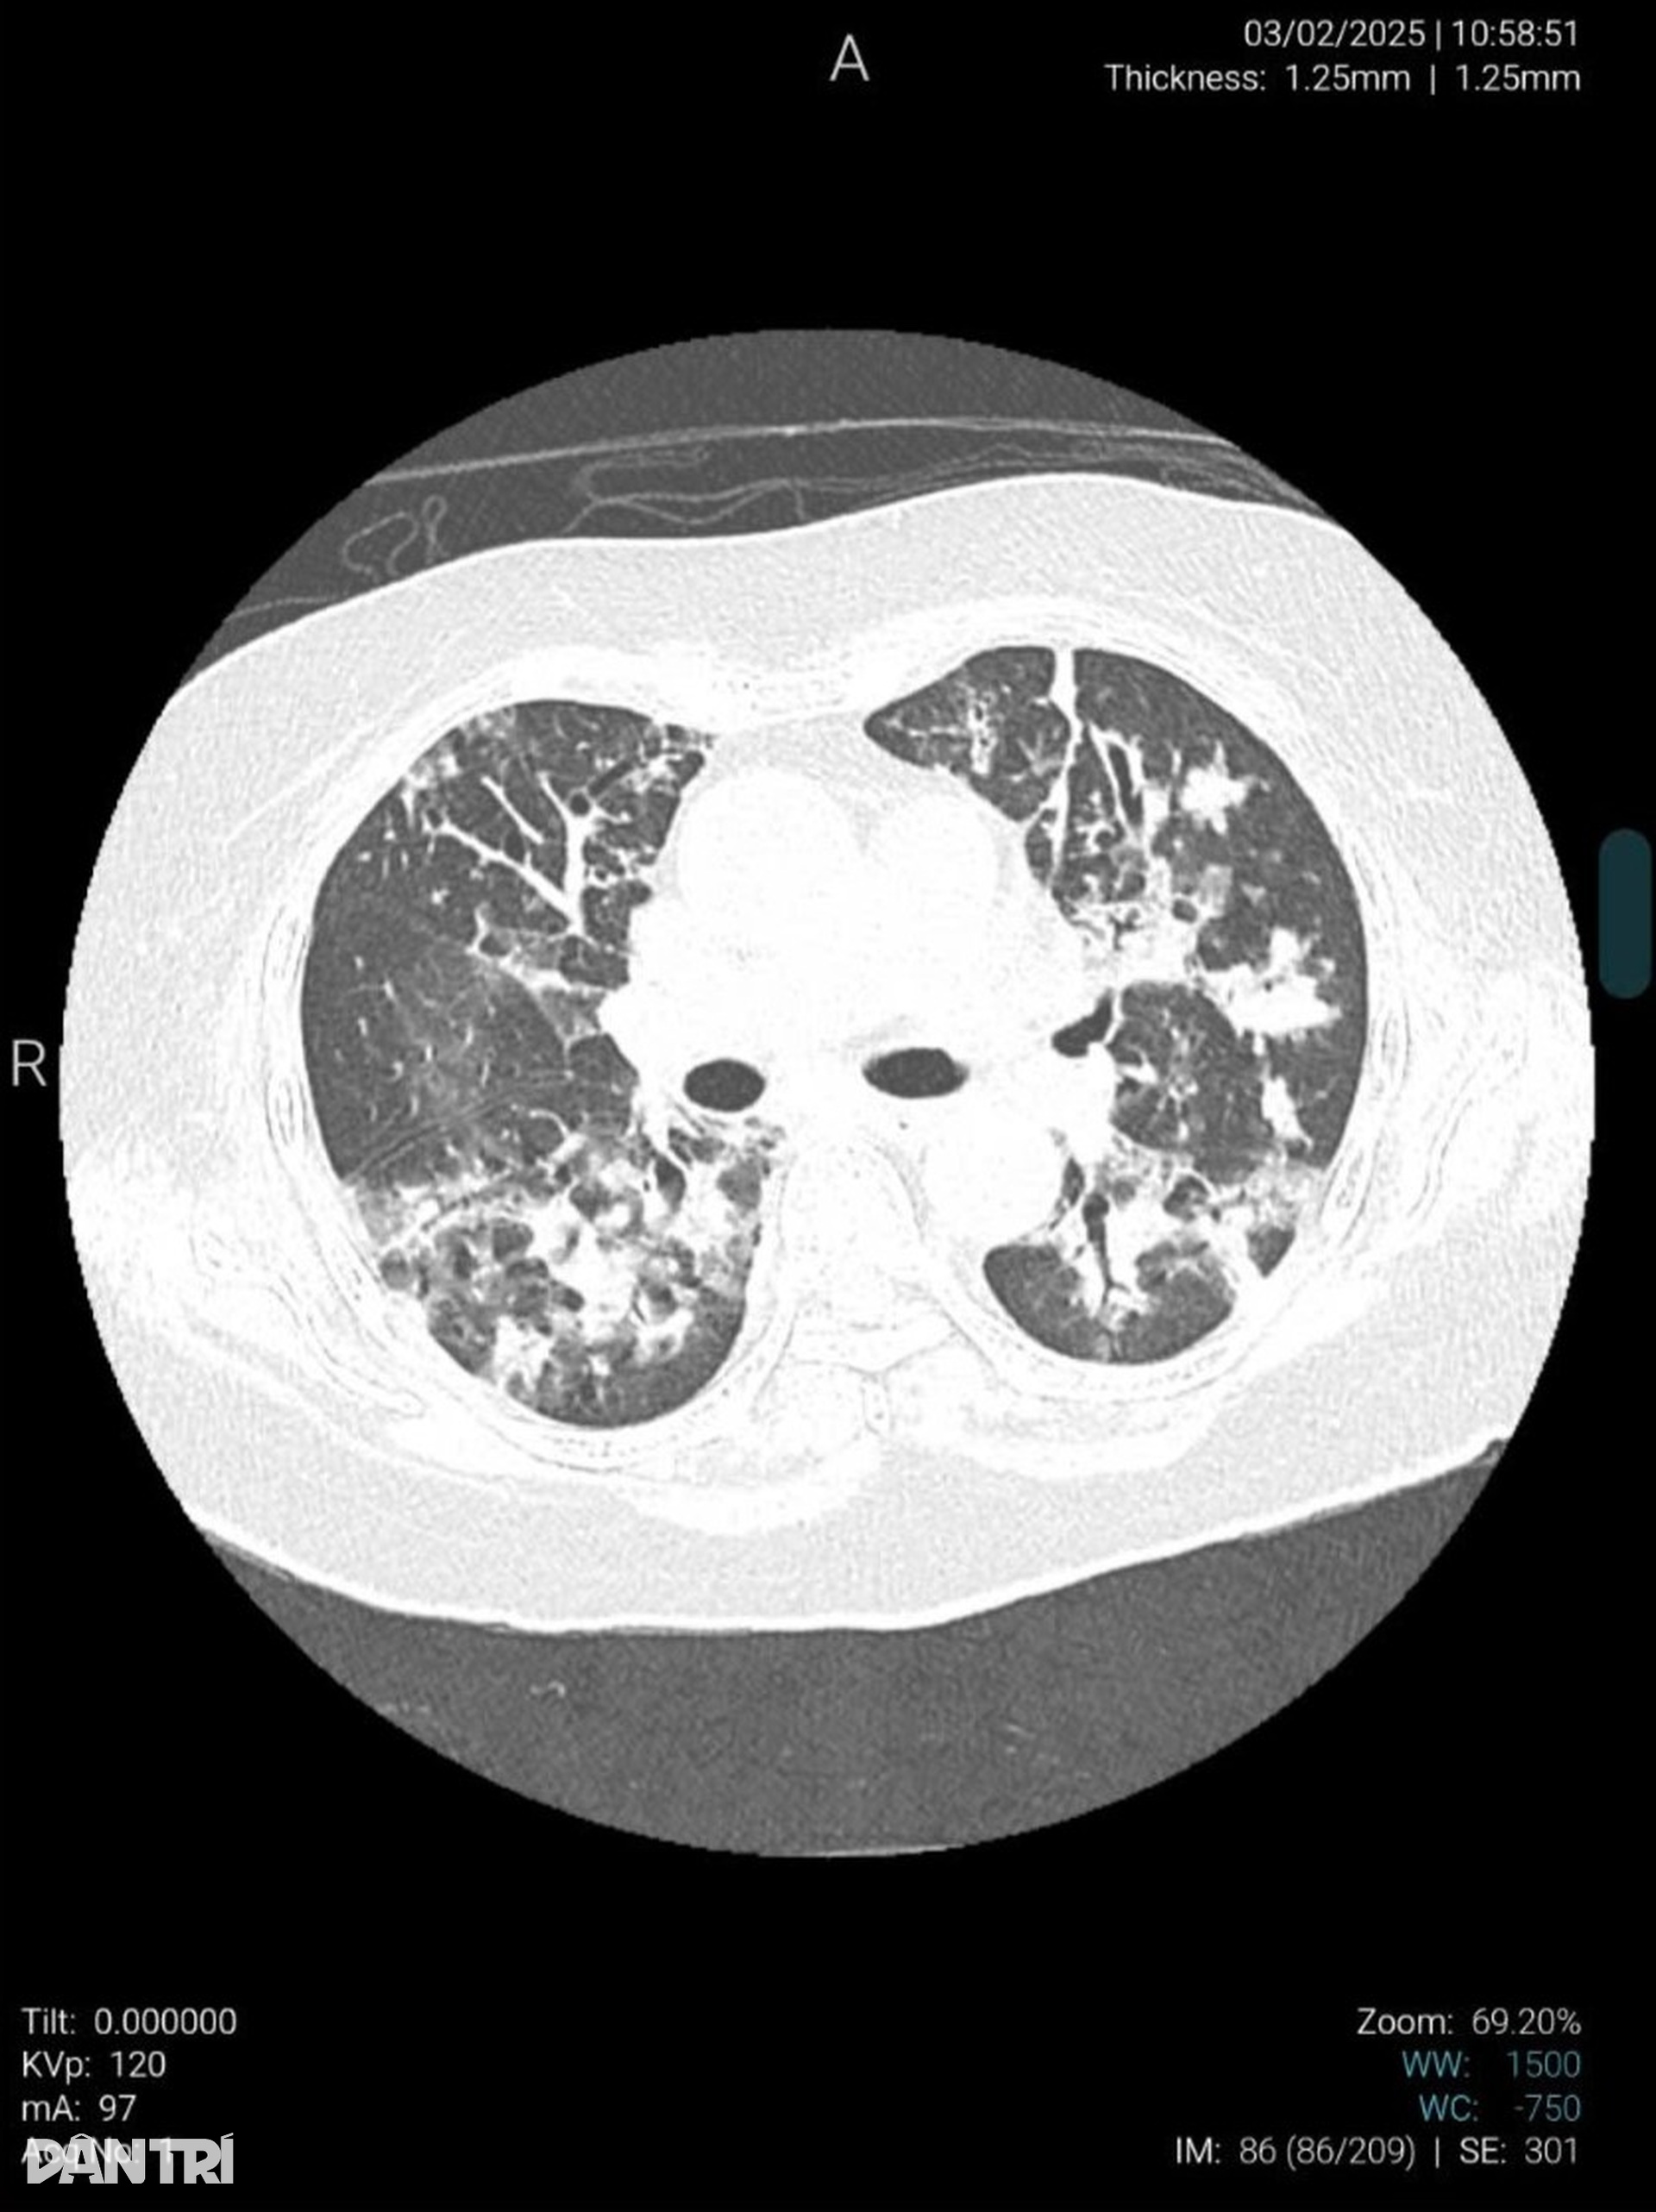

"Đây là bệnh nhân cúm A có biến chứng nặng nhất mà chúng tôi tiếp nhận trong thời gian vừa qua. Phổi bệnh nhân bị tổn thương khoảng 50%. Trên phim chụp X-quang có thể thấy rõ nhiều vùng phổi bị tổn thương có màu trắng xóa", BSCKI Nguyễn Thị Thủy - Phó trưởng khoa Bệnh Nhiệt đới chia sẻ.

Trong vòng hơn 2 tuần, bà Hoa chuyển liên tiếp 3 bệnh viện. Kết quả xét nghiệm cho thấy bà Hoa dương tính với virus cúm A. Ngày 4/2, bà được đưa đến khoa Bệnh Nhiệt đới, Bệnh viện Hữu Nghị (Hà Nội) trong tình trạng tổn thương viêm phổi lan tỏa 2 bên, nấm phổi trên nền viêm phổi kẽ.